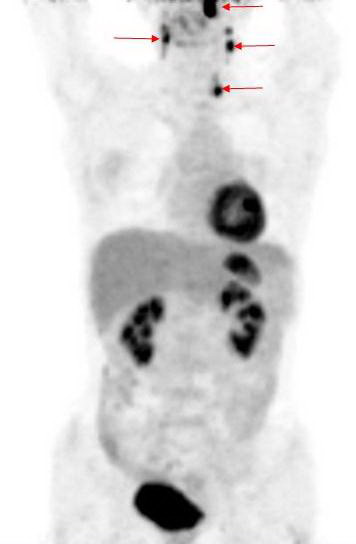

Hình 1: Hình ảnh PET tổng thể cho thấy các tổn thương tăng hấp thu

FDG bất thường tại các vị trí mũi tên

Kết quả PET/CT: tổn thương tăng hấp thu FDG mạnh tại vòm họng bên trái, max SUV=11,8, các tổn thương di căn hạch tại vùng cổ bên phải và bên trái.

Trong khi đó kết quả nội soi vòm họng và CT không phát hiện thấy tổn thương u nguyên phát (CT-) bởi vì tổn thương ở mức độ chưa xâm lấn ra bề mặt niêm mạc vòm họng và mà mắt chưa thể nhận thấy được  qua  nội soi, CT...

Dựa vào các kết quả trên, bệnh nhân được chẩn đoán là ung thư vòm họng di căn hạch cổ hai bên. Đồng thời đánh giá được giai đoạn bệnh của bệnh nhân là T1N2M0, kế hoạch điều trị tiếp theo là xạ trị phối hợp hoá trị.